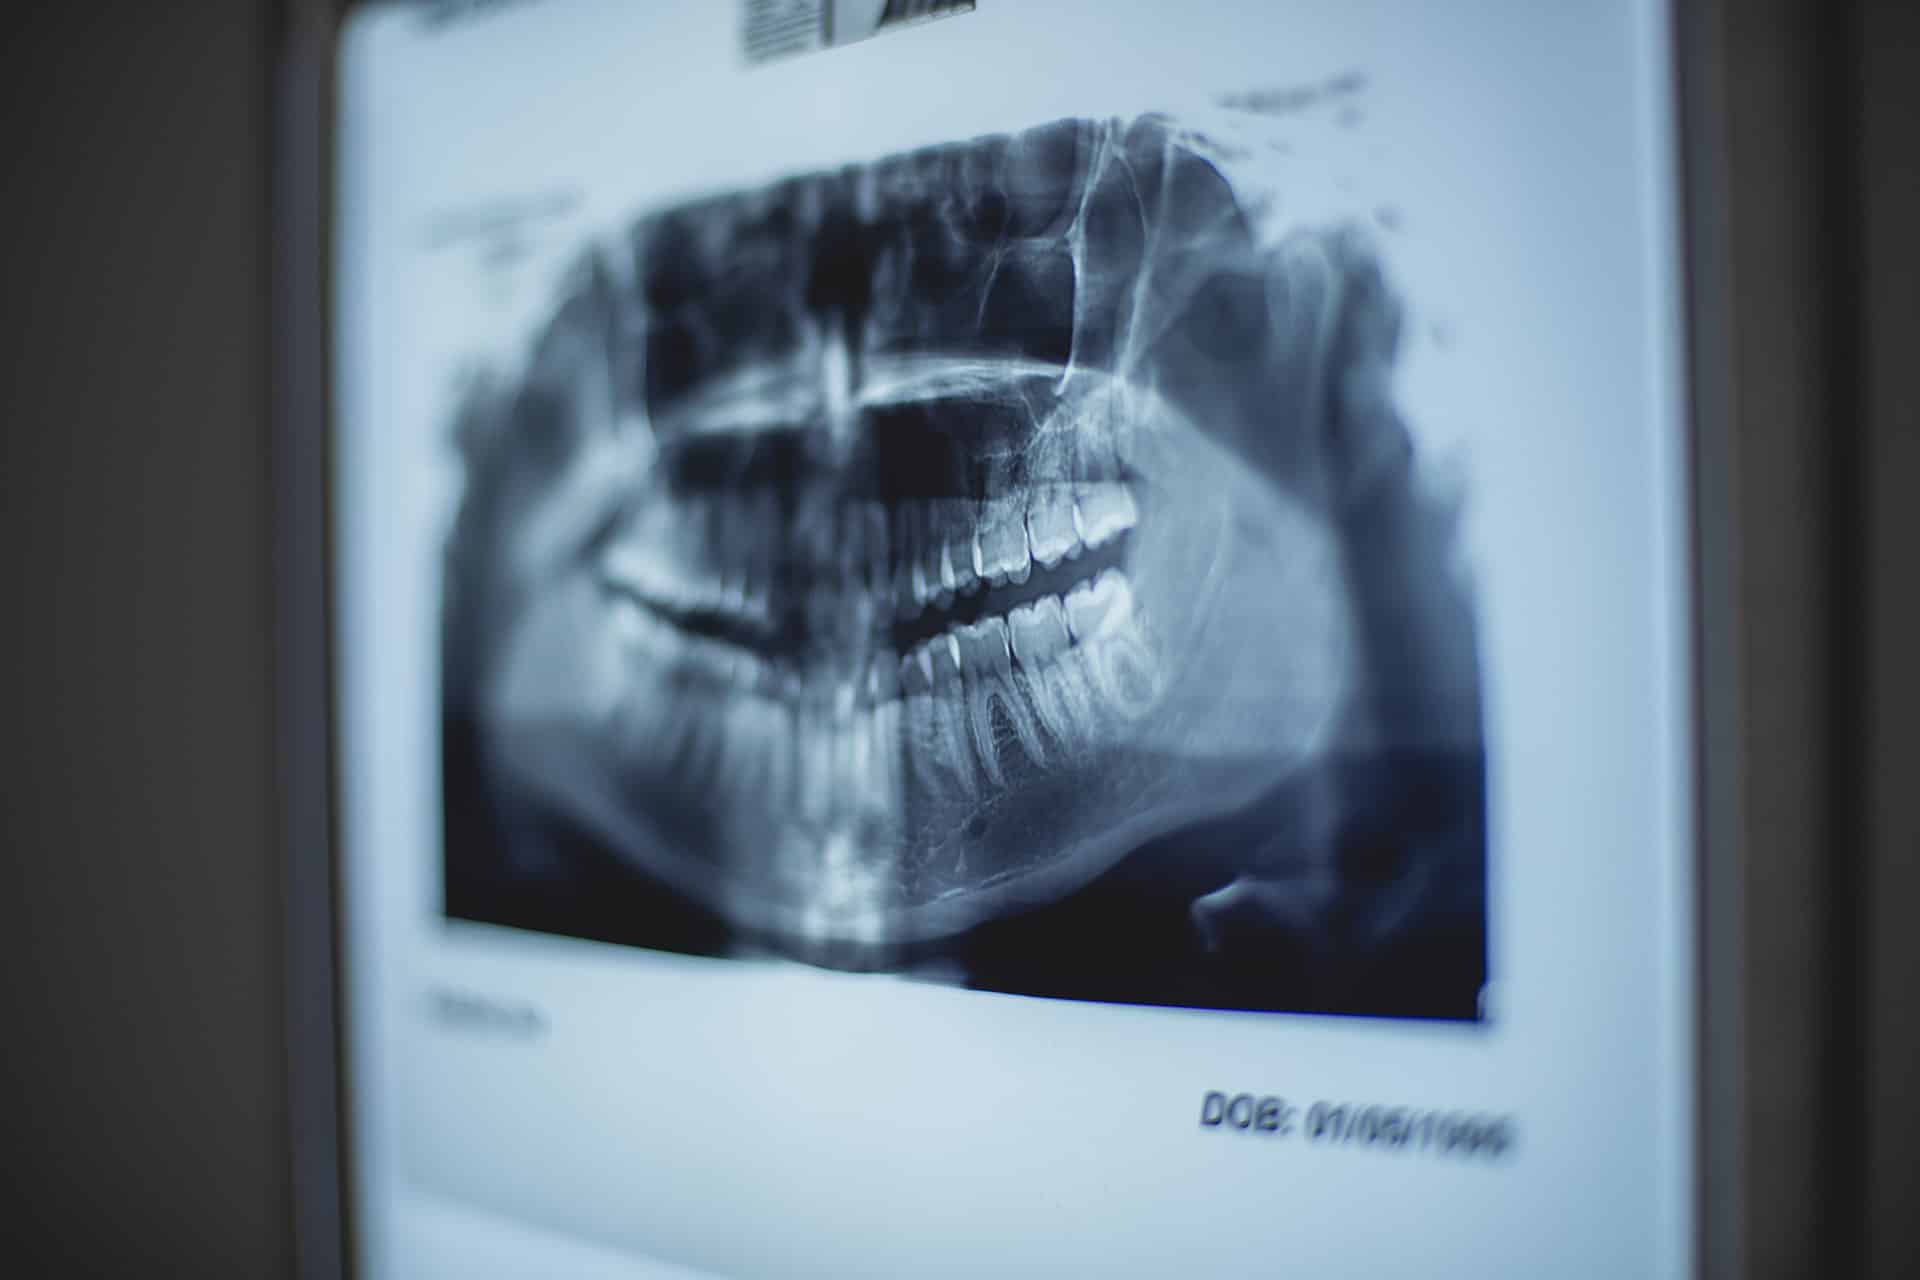

El avance clave en este estudio fue la aplicación de tecnología moderna: la tomografía computarizada permitió superar el principal obstáculo representado por los tejidos blandos momificados que ocultaban la estructura ósea. «El uso de la tomografía computarizada fue un instrumento clave para estudiar el cráneo de la mujer», afirmó Vladímir Kaníguin, jefe del laboratorio de medicina física de la NGU. «Gracias a esta tecnología logramos ‘eliminar’ virtualmente los tejidos blandos y crear un modelo 3D digital —y luego físico— del cráneo, lo que permitió un estudio antropológico detallado».

El escáner utilizado generó cientos de cortes digitales de alta resolución, revelando no solo las secuelas de la lesión, sino también detalles minúsculos invisibles a simple vista o en exámenes convencionales. «La tomografía permitió observar detalles que antes eran inaccesibles», añadió Kaníguin.